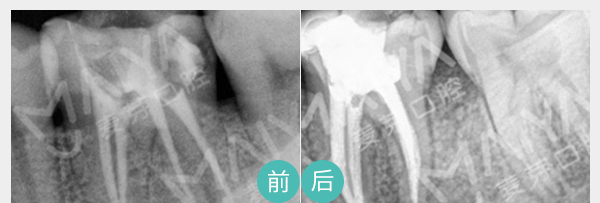

麦芽数字牙周治疗

麦芽数字化牙周治疗有EMS洁牙龈下刮治根面平整、牙周翻瓣术等,根据患者自身情况,设计定制化牙周病治疗方案,从根本上解决病变性牙齿松动。

适应症:牙周炎、牙根吸收引起的轻微牙齿松动